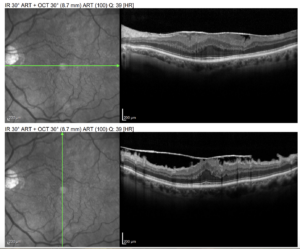

Tomografia de coerência óptica (OCT) macular – olho esquerdo: cortes horizontal e vertical demonstram membrana epirretiniana aderida à superfície interna da retina, com pregueamento das camadas internas, espessamento retiniano e irregularidade da fóvea, levando a perda da depressão foveal normal. Nota-se tração anteroposterior leve e reflexos hiper-refletivos na interface vítreo-retiniana, compatíveis com pucker macular decorrente de membrana epirretiniana.